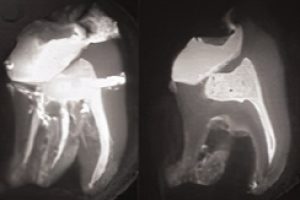

Рентгенологическое обследование у детей

Рентгенологическое обследование у детей необходимо для диагностики, планирования лечения и наблюдения за рядом изменений и патологиями, связанными с зубами и челюстями. Однако, поскольку никакое облучение нельзя считать полностью безопасным, рентгенологическое обследование следует проводить только тогда, когда есть вероятность, что оно принесет пользу пациенту. Например, поспособствует диагностике и / или позволит выбрать наиболее подходящую тактику лечения.